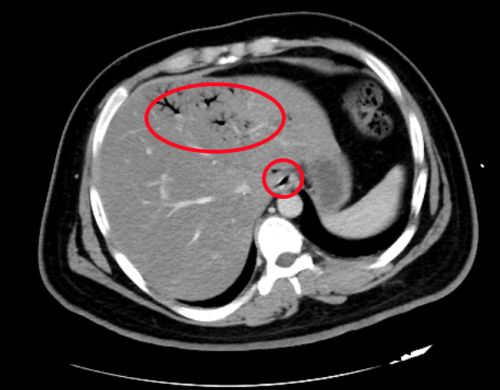

ct显示,肝脏、门静脉、肠壁内都有明显积气(红圈内)。

治疗后积气消失。

进入急诊三科抢救室时,小刘已经神志浅昏迷,呼吸急促,脉搏高达145/分,血压低至休克,快速血糖检测高到“爆表”,只得抽血测血糖,结果显示为123.10mmol/L,超出正常值20多倍!此外,感染指标明显升高;腹部 CT显示:左肝静脉、门静脉、肠系膜静脉及小肠壁积气明显,考虑小肠坏死,随即转入急诊重症病房(EICU)。

“门静脉和肠系膜静脉等出现积气是因为产气细菌进入血液,这种情况在影像学上被称为‘死神之征’,死亡率高达50%”,捷克论坛 急诊三科主任张兴文主任医师表示,小刘由于不良生活方式导致体重超标,并患上糖尿病,在此之前一直没有规范治疗和改变不良生活方式,这次因为肠道菌群失调、移位出现肠源性感染,引发感染性休克,最终导致严重的糖尿病酮症酸中毒(DKA),危及生命。